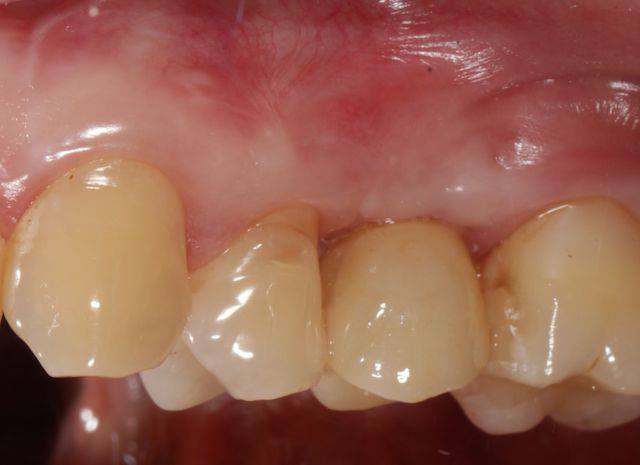

Cette patiente vient me voir pour trouver une solution pour sa 15, que proposez vous?

la dent a eu une résection apicale à l'ancienne il y a quelques années, est mobile, plus d'os en vestibulaire : No way!

J'ai décidé de réaliser un lambeau déplacé latéralement associé à un conjonctif enfoui le jour de l'extraction afin d'avoir des tissus mous de meilleure qualité pour la greffe, ci joint les photos à 6 semaines.